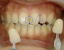

特徴;ほとんど痛みを感じることはなかった症例。

差がわかりやすいように上だけ先にホワイトニングしています。

写真はそのときの写り具合で明るく見えたり暗く見えたりしていますが、上下の歯の色を比較してみて下さい。その差がホワイトニングの差だと感じて下さい。ただ、実物はどの症例ももっと差が歴然としています。

before

6日・・ジェル1本終了

12日・・ジェル2本終了